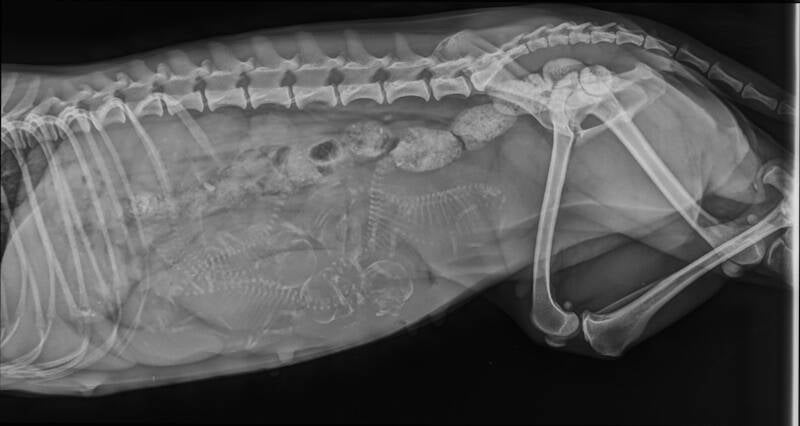

Heute wurde Hedy geröntgt... es sind 5 Babies!!!

Today Hedy was x-rayed ... she carries 5 babies!